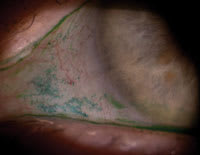

Figure 4. Conjunctival lissamine green staining in a symptomatic lens wearer. |

Along the lines of using vital dyes, lissamine green has essentially replaced rose bengal dye in clinical practice. In evaluating contact lens-related dry eye, lissamine green assessment of conjunctival staining is often the most significant abnormal finding and can be very dramatic (Figure 4). You can also monitor this staining for improvement with treatment.